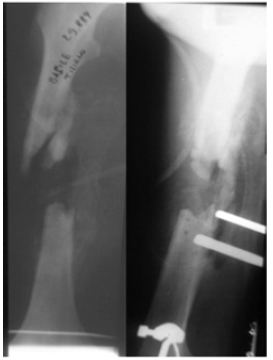

Case No 1

A male, age 18 years had a road traffic accident and sustained multiple injuries. In spite of other injuries was diagnosed as the fracture of femur, clavicle and ribs. He was managed with internal fixation, but it became heavily infected in another hospital. Then he was shifted to our unit for management. As was very weak and had chest problem due to rib fracture so he was initially admitted in intensive care unit. Once he became stable then we managed him with removal of implants and did debridement, but the infection was not controlled. Then in the second stage we removed the dead ends of fracture site that has created created a gap of 11centimeters. To stabilize the bone we applied Lazaro for control of infection and to optimize the patient. At this stage there was no osteotomy done due to the health condition of the patient. The patient was discharged and advised for regular follow up. The patient was very cooperative and very keen in his health. He visited the Lazaro clinic regularly for control of infection. While we were waiting for optimization of his health, we found callus in the gap. We followed him up for six months in Lazaro and found that all the of gap was filled with new bone and healed without any intervention (Figures 1-6).